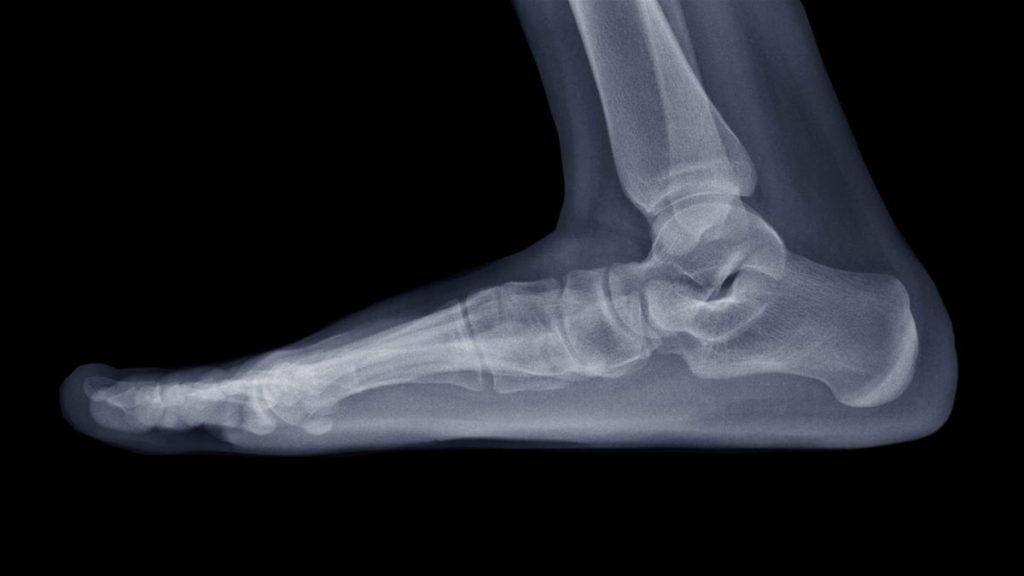

Along the inside of the foot is a raised area called the medial longitudinal arch. In flatfoot, this arch is lower than normal—or completely flattened—often accompanied by heel valgus, where the upper heel tilts inward relative to the lower leg.

- Flatfoot happens when the talus bone “collapses” downward, the heel tilts inward, and the posterior tibial tendon is stretched trying to support the arch.

Diagnosis usually requires only a physical exam. X-rays or other imaging tests are performed if the pain is significant.